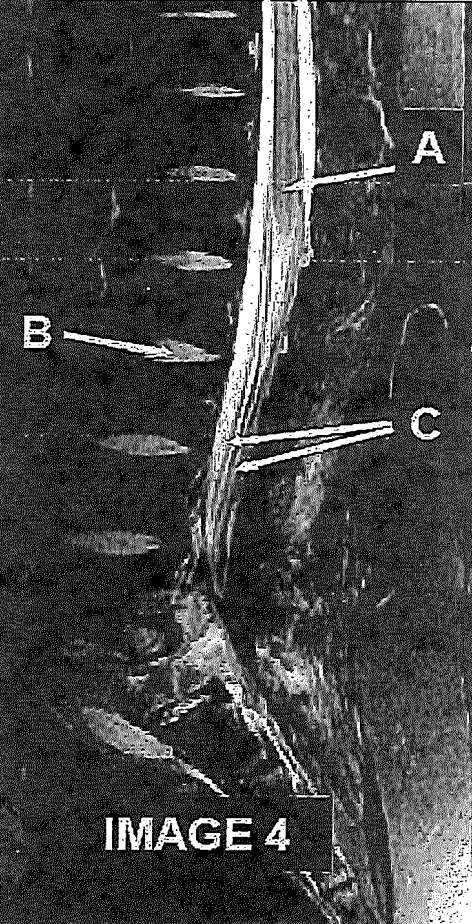

Which letter demonstrates the cervical nerve root exit foramina?

A

C

Q

What letter demonstrates the intervertebral disc?

B

17

What letter demonstrates the conus medullaris?